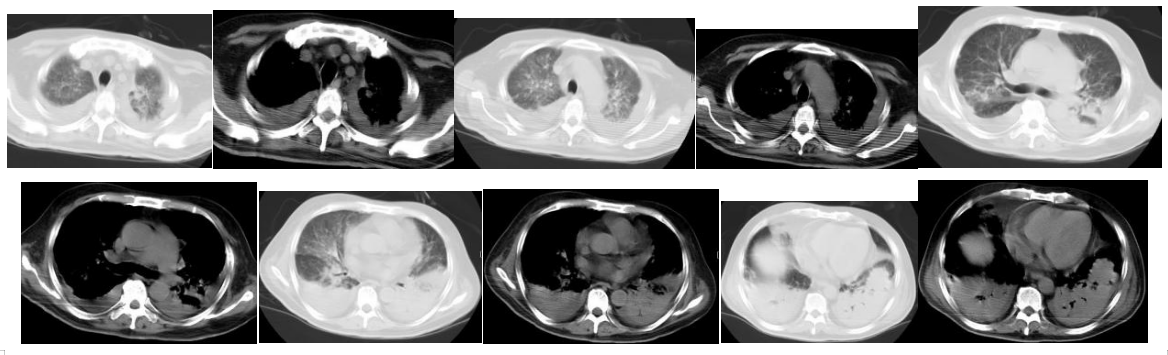

CT(2023-05-22):双肺存在散在的渗出病变,见图1。

CT(2023-06-28):双肺散在渗出进展为实性病变,下肺为主,见图2。

图1. 入院前胸部CT(2023-05-22)

图2. 门诊胸部CT(2023-06-28)